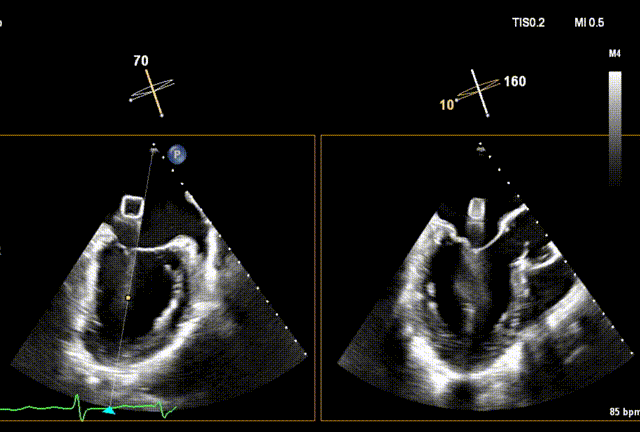

术前经食道超声(TEE)评估

术前TEE

DMR P2脱垂连枷(脱垂范围:12mm,连枷间距:3mm),反流2区,MR重度(VC:4* 10mm),A2:21mm,P2:10mm,AP:30mm,MVA约 4.7 cm²。